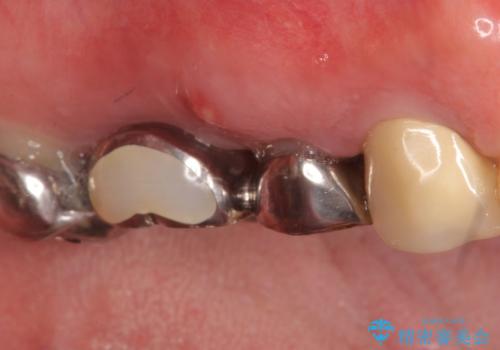

右上の567ブリッジを外したところ、右上5は歯根破折により保存不可能だったため、右上56部にインプラントを埋入し欠損補綴を行いました。

また右上5部に関しては抜歯時に歯槽堤保存術(抜歯窩に人工骨の填入を行う手術)を行い、骨の欠損を最小限に止めています。